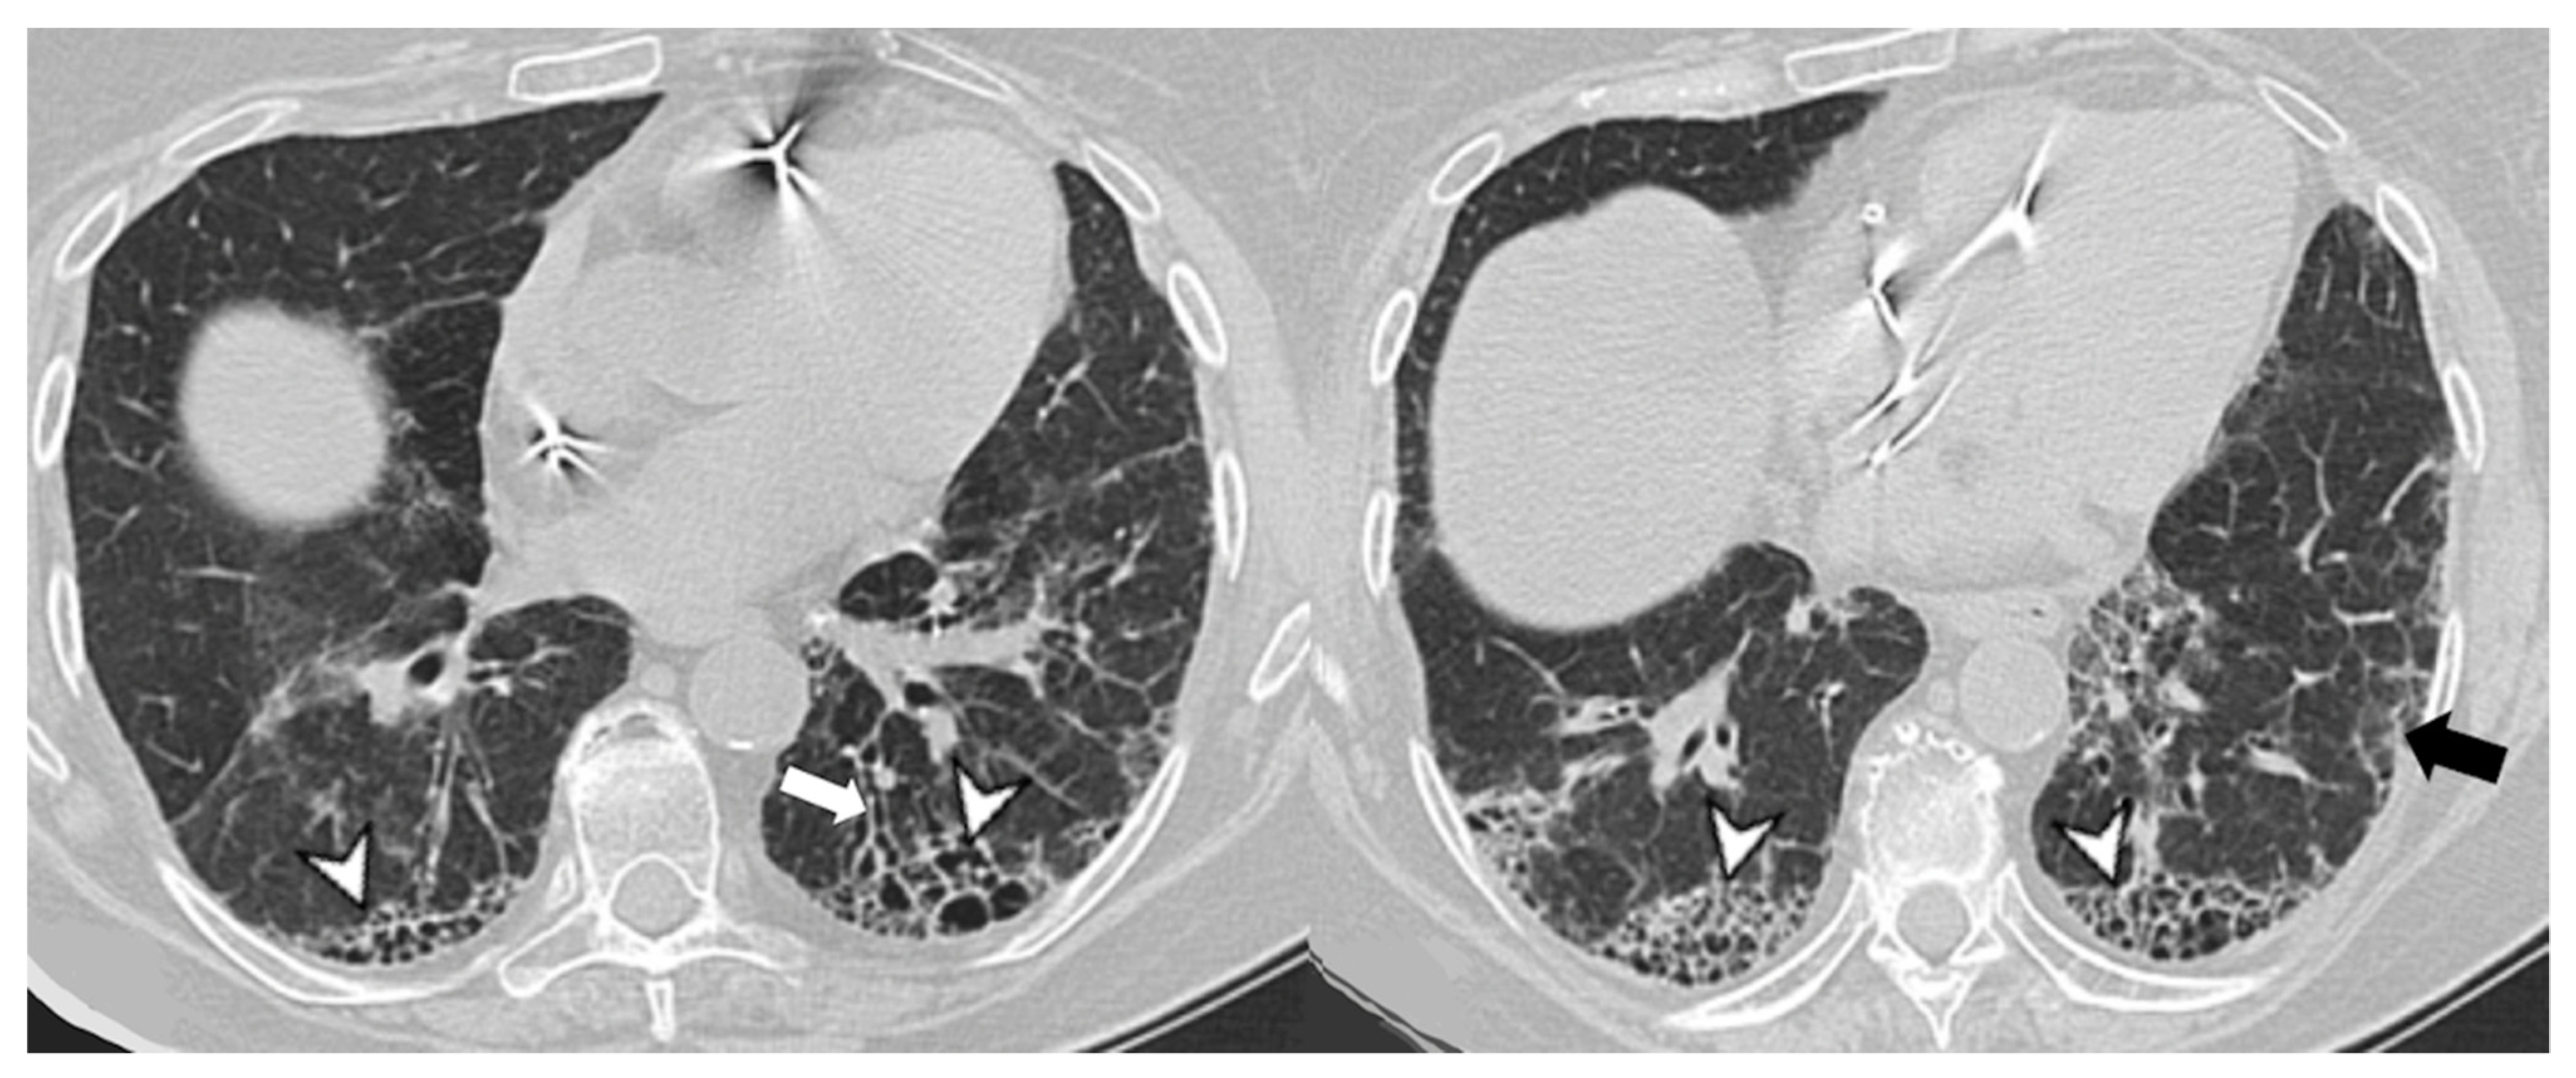

4.2.1. HRCT Findings of Patients with Anti-ARS Abs

| Lesions | GGO, reticulations, consolidations | consolidations, GGOs | |

| Distribution | Homogeneous; lower lung lobes, along bronchovascular bundles and lung periphery; loss of volume of lower lobes | Patchy; peripheral lower lobes or along the bronchovascular bundles | |

| CT pattern | NSIP OP NSIP-OP UIP DAD-unclassifiable | 50% 20% 25% 10% +/− | 20% 50% 25% <5% ++ |